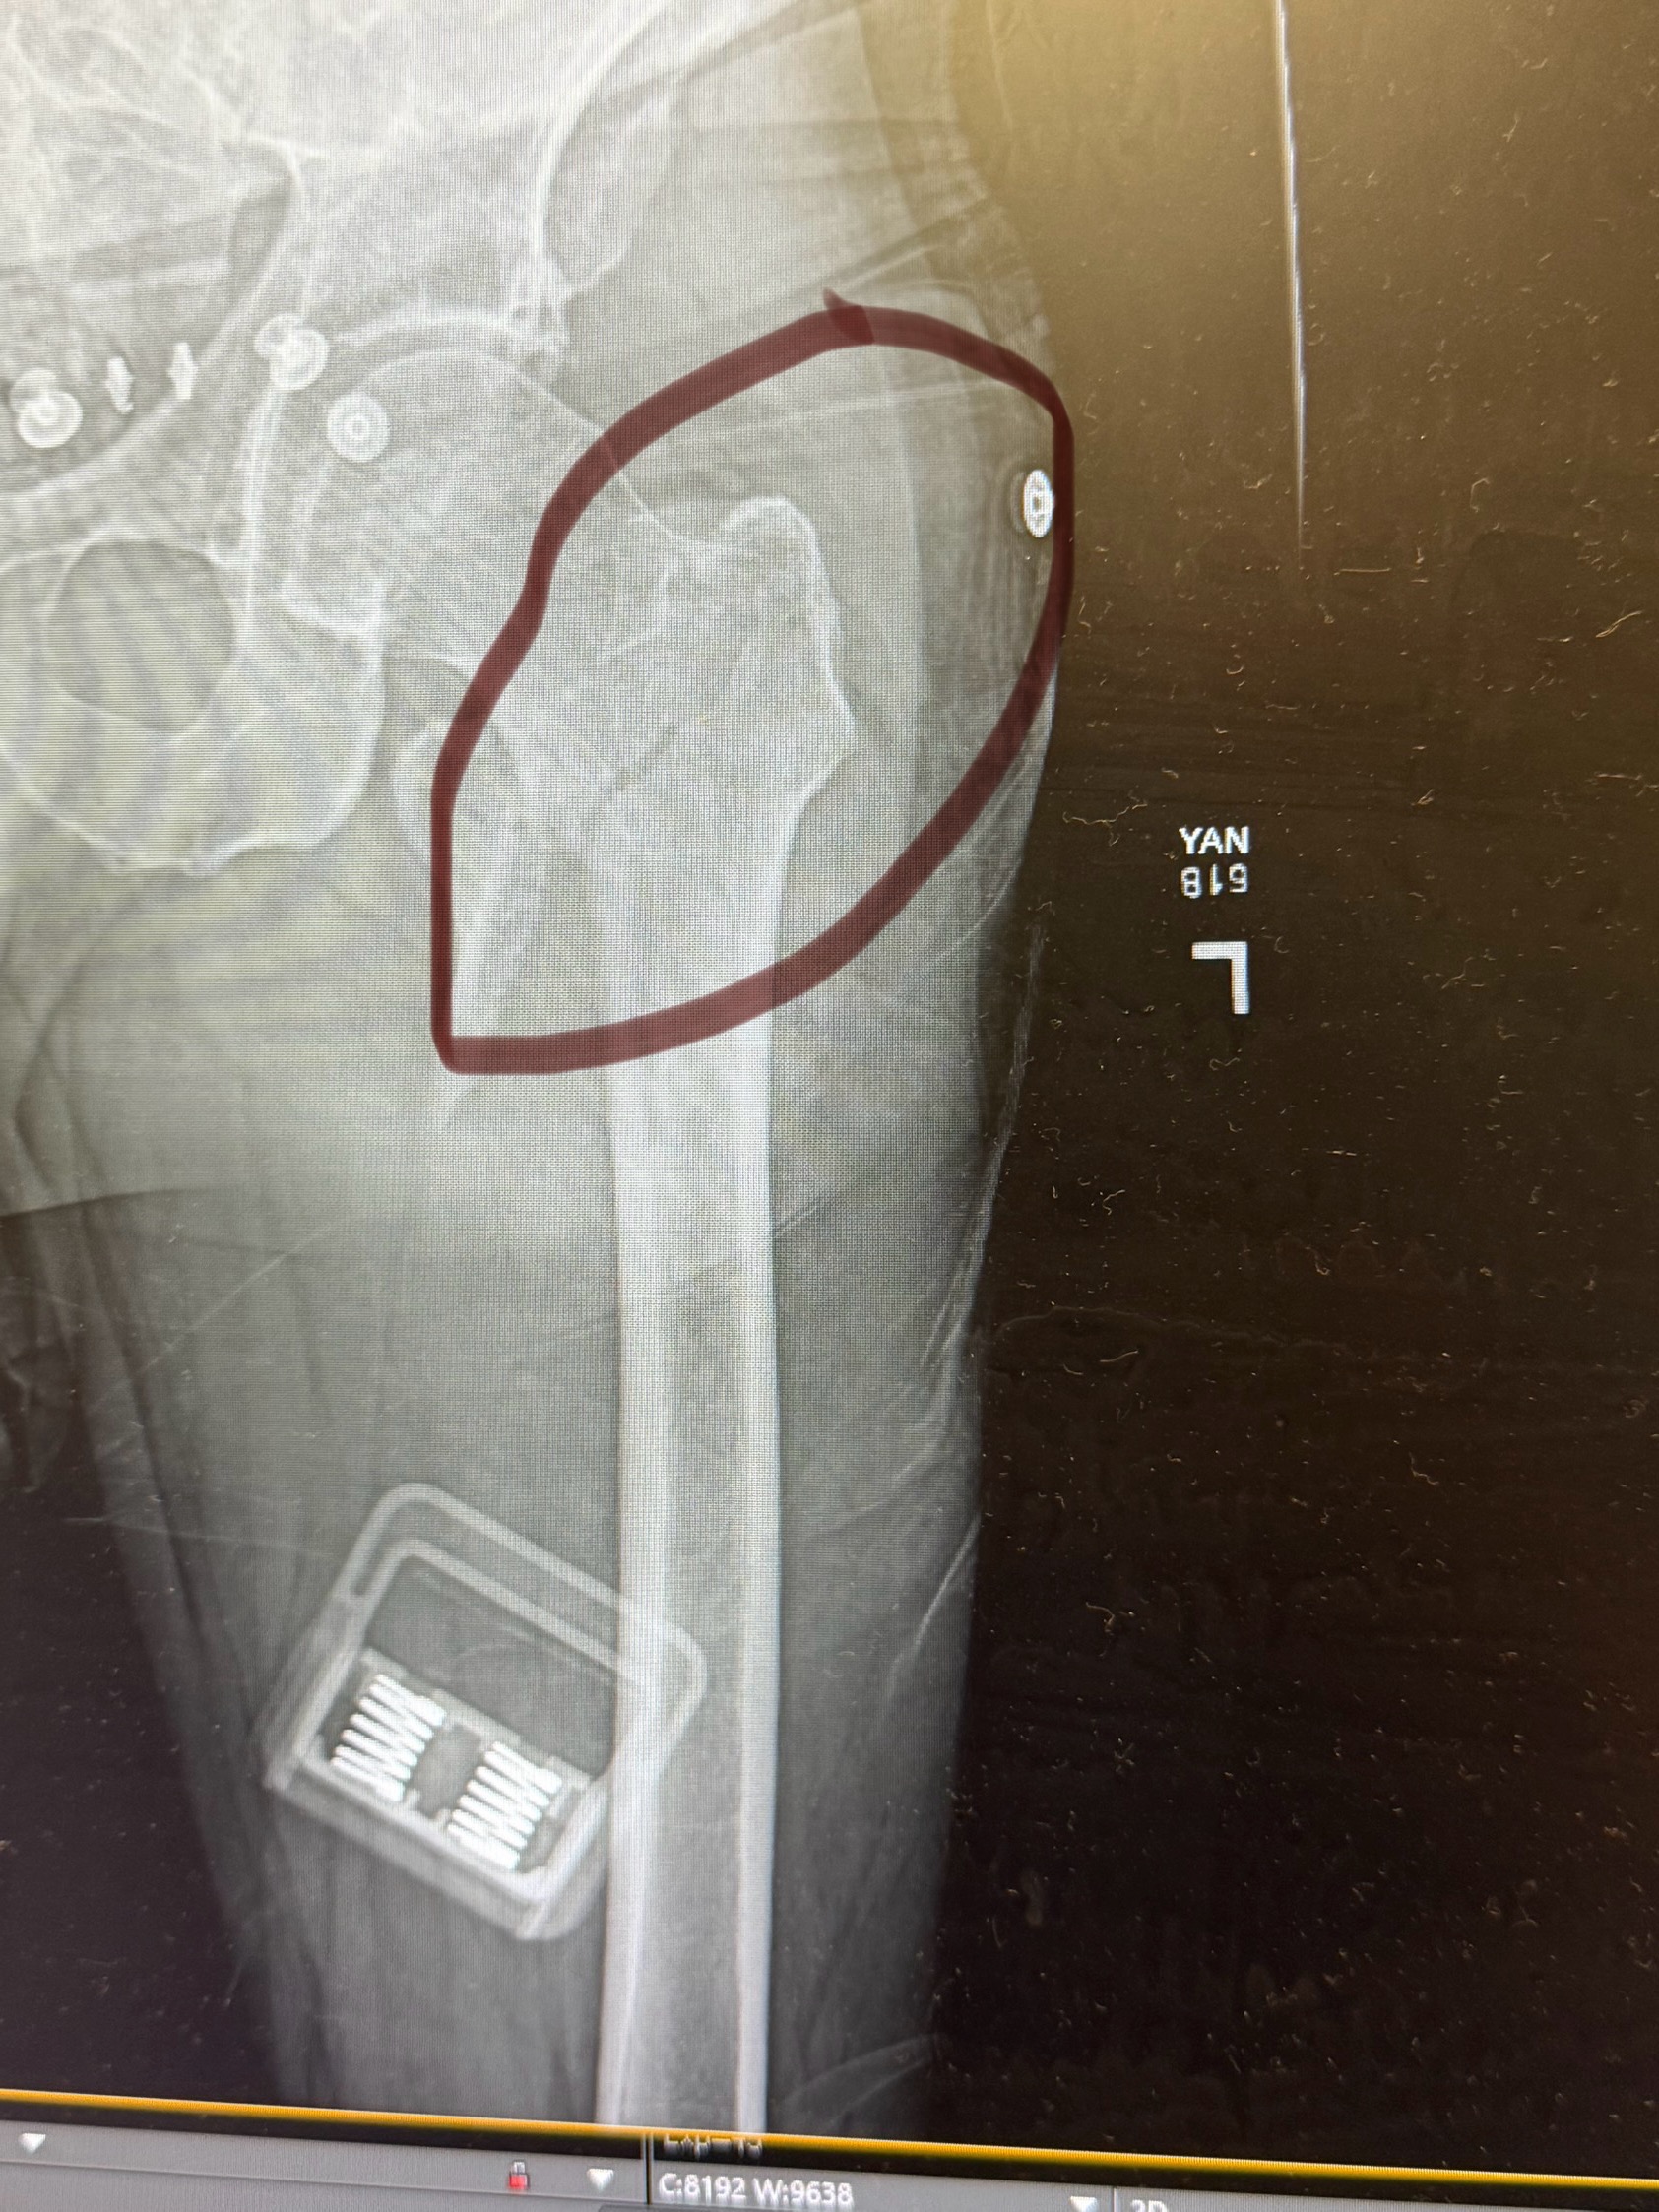

On 6/4/25, Jon was brought into surgery to have a rod (or two), two bands, and six screws placed in his thigh to hold the rods in place. He was released from the hospital on 6/5/25 with pain medication and instructions to remain at home, rest, continue follow-up appointments, and start therapy in a couple of weeks.

staples out today and more x-rays done. The rod goes directly into his femur. As of right now, he’ll be out of work at minimum another 5 weeks. Then another recheck with the surgeon. Physical therapy starting next week